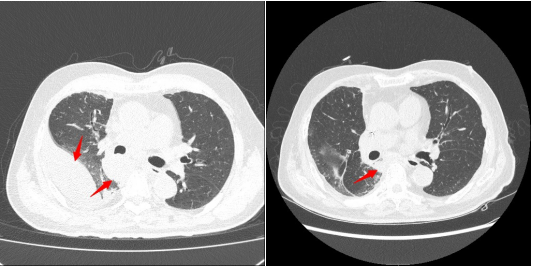

患者为76岁男性,三个月前突发右侧胸痛伴胸闷,症状进展迅速,一周后需持续吸氧。当地医院检查发现右侧大量胸腔积液,胸部CT提示右肺门巨大占位,伴胸膜肿物及纵隔淋巴结肿大。转入清华大学附属垂杨柳医院胸外科后,经团队行经支气管超声引导纵隔淋巴结穿刺活检,病理确诊为肺肉瘤样癌,PD-L1表达大于90%,PET-CT进一步明确为晚期病变。

针对该患者病情特点,胸外科团队制定了化疗联合免疫治疗的个体化方案。2025年11月下旬及12月中旬,患者分别完成两个周期的白蛋白紫杉醇+卡铂联合帕博利珠单抗治疗。治疗后患者胸闷、喘憋等症状显著缓解,影像学复查显示右肺门肿瘤及胸膜多发转移病灶均明显缩小,治疗效果显著。目前患者整体病情得到有效控制,已出院继续接受恢复性治疗。